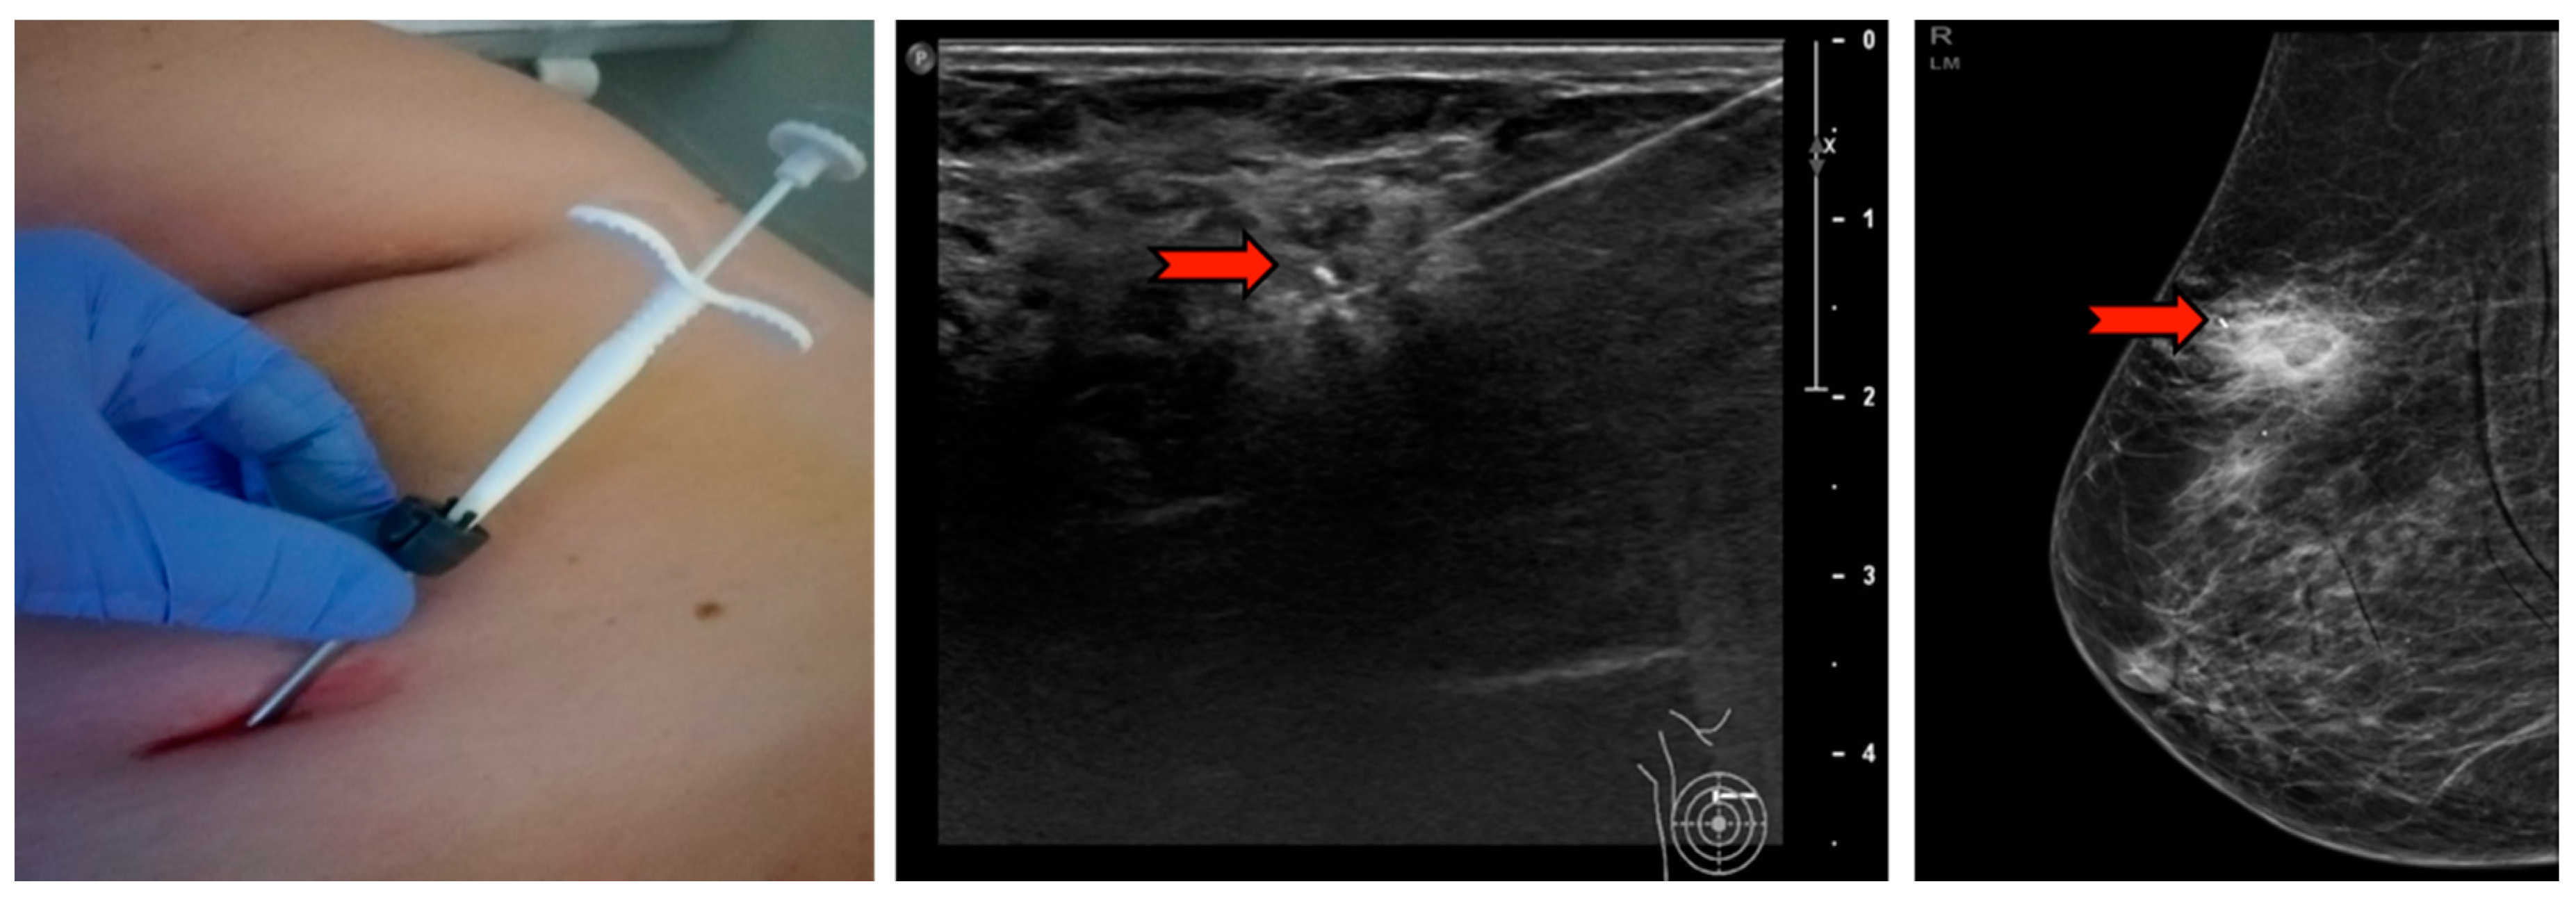

Samples obtained using Elite, more than three times the weight and volume compared to CB (approx. 60 vs. 12 g), are collected automatically and extracted, avoiding any external contact, into a small radio-transparent container fixed to the base of the handpiece (Figure 3 and Figure 4). The samples are fixed in formalin and sent to the Department of Pathological Anatomy. At the end of the procedure, in order to relocate the site, a small non-magnetic clip may be inserted, which is visible in mammography and ultrasound for up to a maximum of 6 months, in cases of lesions that could mutate over time, such as complex cysts or tumors needing neoadjuvant therapy (Figure 5).

Figure 2. Workflow of the VABB Elite procedure. The biopsy finding is initially identified on the ultrasound; 5–10 mL of lidocaine s.c. is then administered (perilesional subcutaneous); the biopsy needle is visualized by ultrasound (red arrow in the figure) until the sampling site is reached; the procedure is started with a 360° rotation at the pick-up, cutting and automatic suction of the whips in the collection container located at the base of the handpiece; at the end of the procedure it is possible to extract the needle and the handpiece, leaving in place a cannula for the insertion of a localization clip visible in ultrasound and mammography up to 6 months after the procedure.

Figure 5. The needle and handpiece extraction and subsequent insertion of the localizing clip in the cannula left in the biopsy site. The red arrow indicates the clip in mammography and ultrasound that will be visible in follow-ups for up to 6 months.